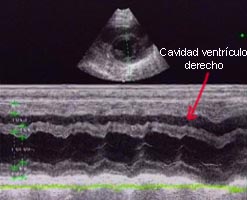

Algunos de los síntomas clínicos son característicos de un fallo cardíaco, por ello desarrollamos un examen ecocardiográfico a los animales. En modo B, se aprecia una cardiomegalia generalizada con una prominencia importante del ventrículo y el atrium derecho (la sobrecarga del volumen ventricular provoca una dilatación diastólica ventricular apreciándose un grosor de pared normal, una función sistólica normal y una hipertrofia excéntrica). En modo M se observa un movimiento paradójico del septo interventricular secundario a la sobrecarga del volumen ventricular derecho. La mayoría de los corazones estudiados muestran una pequeña efusión pericárdica y áreas hiperecogénicas en el miocardio del septo interventricular. En Doppler de flujo de color se aprecian turbulencias en la arteria pulmonar y en las válvulas auriculo-ventriculares.

Ecocardiografía en modo M. En la imágen de la izquierda se observa un corazón normal, mientras que en la de la derecha se detecta una pérdida del ritmo de las contracciones con un movimiento paradójico del septo interventricular, además se observa el ventrículo derecho debido a la dilatación. |